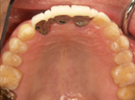

54歳女性

部分義歯がどうしても違和感が強くて、できれば義歯を使わなくてもいいようにしたいとのこと。

下顎はそんなに問題ないですが、上顎は骨の厚みと量、共に乏しく本来はインプラントは不可能です。

あきらめずに、かなり高度な技術ですが骨を増やす手術を併用してなんとか植えることができました。

術前

↓↓↓↓

術後